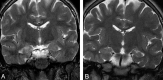

Results: Thirty-three of 42 patients (78.6%) demonstrated enlargement and T2 hyperintensity of mesial temporal lobe structures at some time point. Mesial temporal sclerosis was commonly identified (16/33, 48.5%) at follow-up imaging. Six of 9 patients (66.7%, P = .11) initially demonstrating hippocampal enhancement and 8/13 (61.5%, P = .013) showing hippocampal restricted diffusion progressed to mesial temporal sclerosis. Conversely, in 6 of 33 patients, abnormal imaging findings resolved.

Conclusions: Autoimmune voltage-gated potassium channel complex encephalitis is frequently manifested as enlargement, T2 hyperintensity, enhancement, and restricted diffusion of the mesial temporal lobe structures in the acute phase. Recognition of these typical imaging findings may help prompt serologic diagnosis, preventing unnecessary invasive procedures and facilitating early institution of immunotherapy. Serial MR imaging may demonstrate resolution or progression of radiologic changes, including development of changes involving the contralateral side and frequent development of mesial temporal sclerosis.